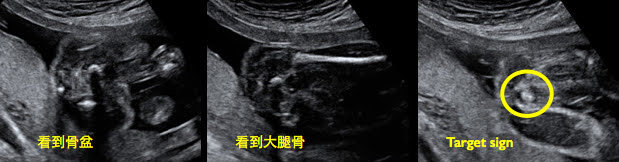

第二個direct finding--anal mucosa 跟第一個PAMC是類似的概念,只是多看了 PAMC 內側的 anal mucosa, 超音波下的黏膜呈高回音,所以高回音外包圍一圈低回音肌肉時,看起來就像標靶,故稱為 target sign[7] (圖3)。

產前超音波找target sign時要注意切面的位置,必須周圍沒有任何骨盆腔的骨頭或大腿骨,才能找到正確的 target sign (圖4)。 Perlmen曾於 2014年發表文章指出不正確的切面會把 ischial tuberosity 的高回音誤認為 anal mucosa (圖5),必須當心。文中也指出,看到anal mucosa還是無法排除最輕微的無肛症--僅有一層薄膜覆蓋在肛門,去除薄膜後,肛門的構造和功能完全正常。

圖3. Target sign (參考資料:Prenatal Diagnosis 2014, 34, 1307–1311)

| 圖4. 找 target sign 正確平面,不能有骨盆或大腿骨 (參考資料:台兒診所) |